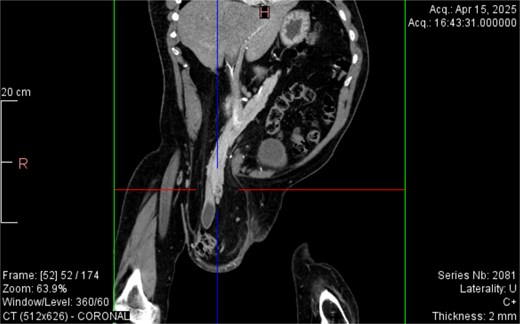

CT imaging (Figs 2–5) revealed a right inguinal hernia containing small bowel loops, ascending colon, the second and third portions of the duodenum, and the pancreatic head. The pancreatic head appeared rotated and displaced inferiorly into the hernia sac, without signs of acute pancreatitis.

Coronal CT view visualization of vascularization of pancreatic head after i.v. contrast.